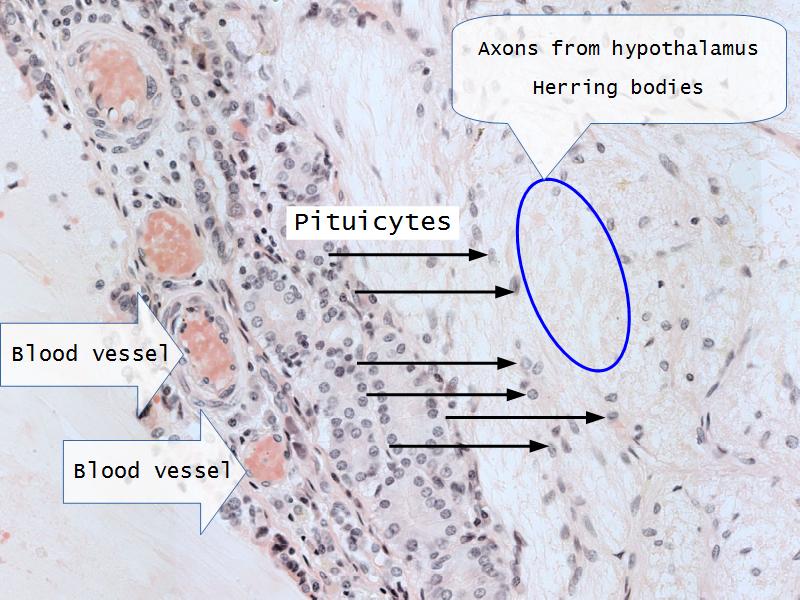

- E2: Oxytocin

- E3: Vasopressin

- E2: Oxytocin = neurons in the hypothalamus

- E3: Vasopressin = neurons in the hypothalamus

- E4: PTH = Chief cells in the parathyroid

- F2: Pituicytes

- F2: Pituicytes = pars nervosa of the posterior pituitary

- Slide 52: Pituitary gland

Pituitary gland

How does the pituitary and hypothalamus communicate?2 ways